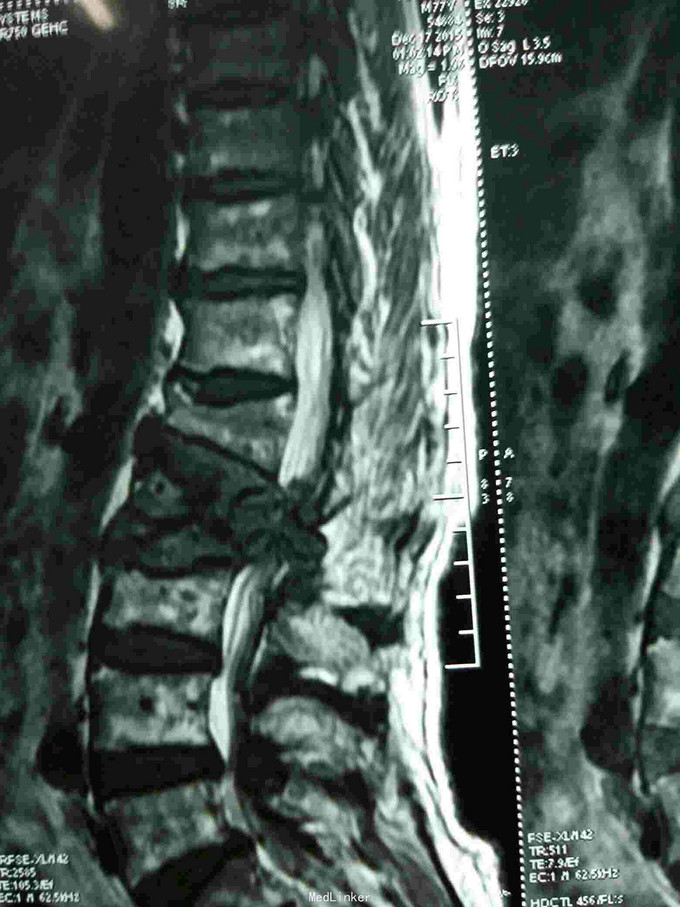

根据病史查体诊断:腰间盘突出症待确诊。应用消肿营养神经镇痛治疗。一天。查核磁共振示:腰椎多节段间盘突出伴椎管狭窄。第二腰椎骨破坏侵及椎板。部分突入椎管,脊髓受压。诊断:腰间盘突出伴椎管狭窄。第二腰椎转移癌,脊髓受压。经与家属沟通,查双肺CT:双肺下叶炎症。肺部纤维化。可见肿瘤阴影。肋骨及胸膜受累。胸椎部分骨破坏。最终诊断:双肺癌,胸椎,腰椎骨转移,脊髓受压。多节段腰椎间盘突出。病人至肿瘤科治疗。